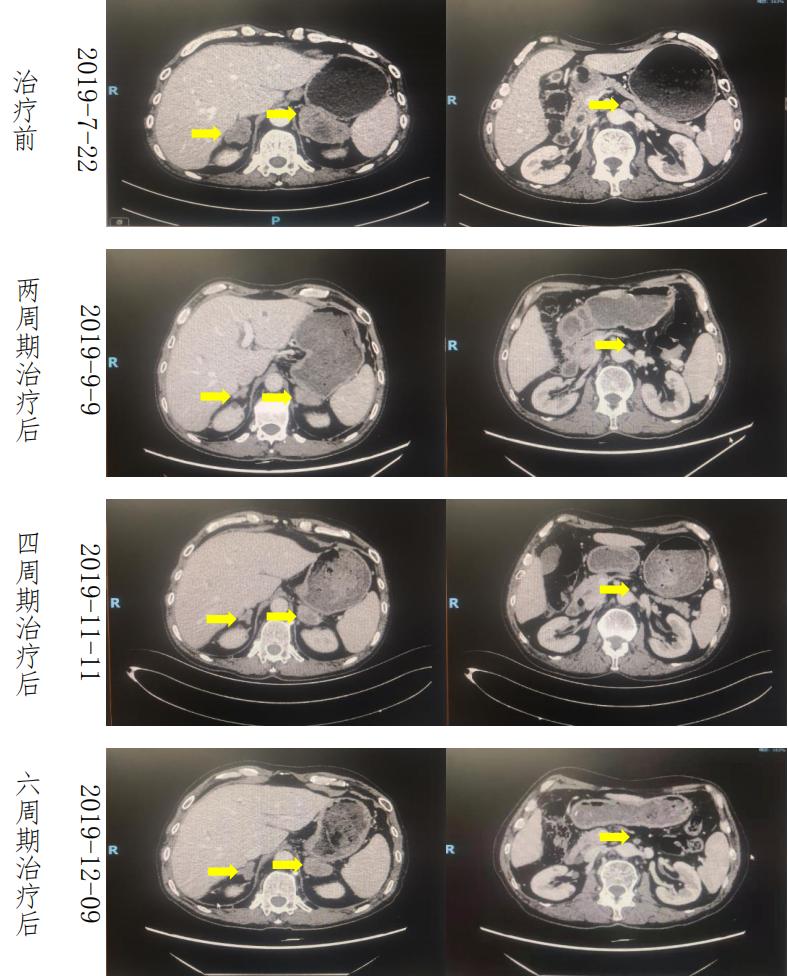

疗效评估 :一线 Xelox 方案化疗 2 周期后肾上腺肿瘤明显退缩,腹膜后淋巴结明显缩小,疗效评估(PR),一线方案治疗 6 周期后疗效评价(SD),肿瘤稍增大;一线治疗 4 周期后血 CA199 出现回升,6 周期治疗后 CA199 明显升高。